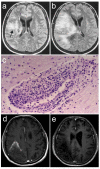

Progressive multifocal leukoencephalopathy is caused by the JC polyomavirus (JCV) and is one of the most feared complications of HIV-1 infection. Unlike other opportunistic infections, this disease can present when CD4 counts are higher than those associated with AIDS and when patients are receiving combined antiretroviral therapy, either shortly after starting or, more rarely, during long term successful treatment. Clinical suspicion of the disease is typically when MRI shows focal neurological deficits and associated demyelinating lesions; however, the identification of JCV in cerebrospinal fluid or brain tissue is needed for a definitive diagnosis. Although no specific treatment exists, the reversal of immunosuppression by combined antiretroviral therapy leads to clinical and MRI stabilisation in 50-60% of patients with the disease, and JCV clearance from cerebrospinal fluid. A substantial proportion of patients treated with combined antiretroviral therapy develop inflammatory lesions, which can be associated with either a favourable outcome or clinical worsening. The reasons for variability in the natural history of progressive multifocal leukoencephalopathy and treatment responses are largely undefined, and more specific and rational approaches to management are needed.